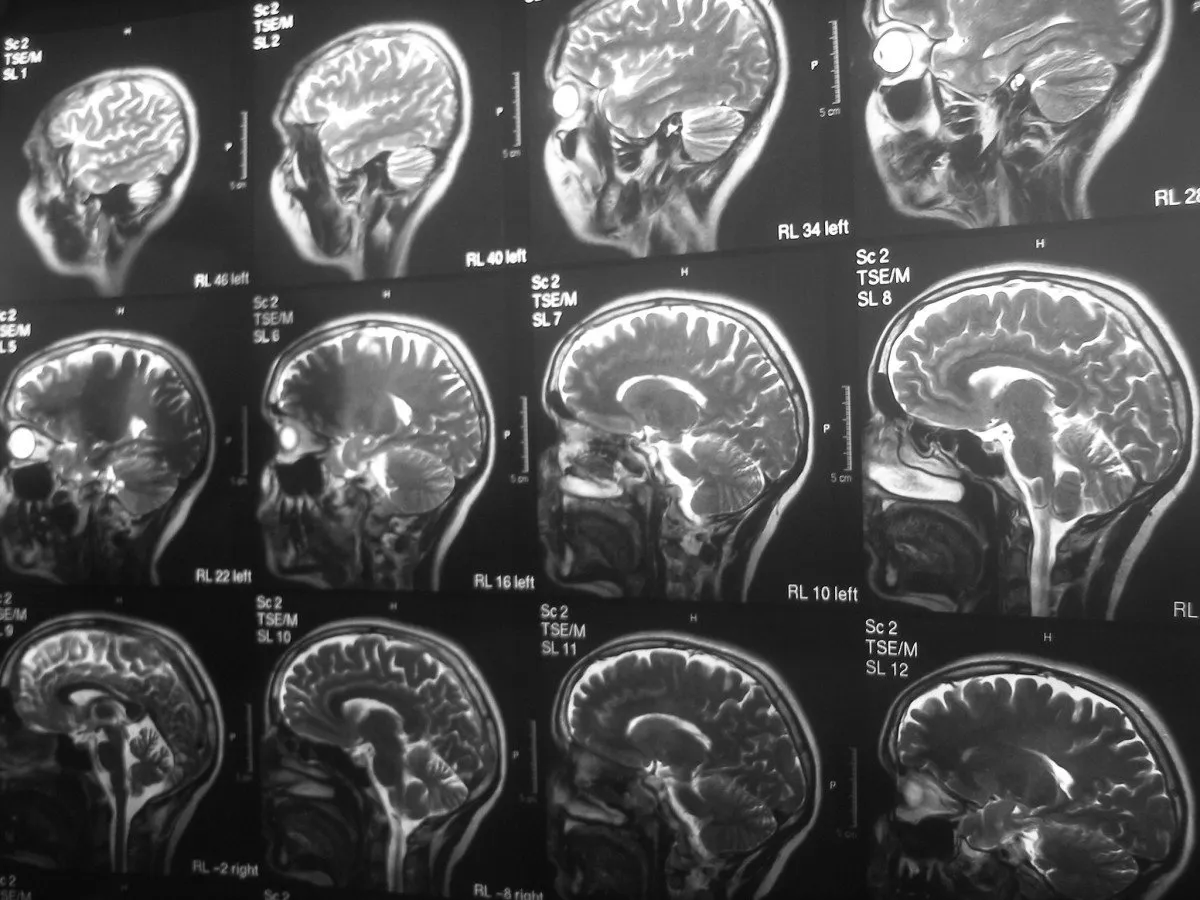

Pod wpływem psychodelików obserwuje się znaczącą desynchronizację i dezorganizację aktywności neuronalnej w mózgu. Normalnie, komunikacja między różnymi obszarami mózgu jest uporządkowana i zsynchronizowana. Psychodeliki zakłócają ten ustalony porządek, prowadząc do swoistego "resetu" w komunikacji nerwowej. Ta tymczasowa dezorganizacja nie jest jednak chaotyczna w negatywnym sensie; wręcz przeciwnie, przygotowuje grunt pod nowe sposoby przetwarzania informacji i tworzenia połączeń neuronalnych, co jest kluczowe dla doświadczania psychodelicznego stanu.

Wyciszenie DMN i desynchronizacja aktywności w mózgu prowadzą do stanu, który naukowcy określają jako "zwiększona entropia". W kontekście mózgu oznacza to większą elastyczność, plastyczność i zdolność do tworzenia nowych połączeń. Mózg staje się bardziej "połączony" w tym sensie, że globalna konektywność funkcjonalna czyli intensywność wymiany informacji między różnymi, często odległymi obszarami mózgu znacząco wzrasta. Obszary, które normalnie działają w izolacji, zaczynają ze sobą "rozmawiać", tworząc tymczasowe, nietypowe sieci neuronalne.